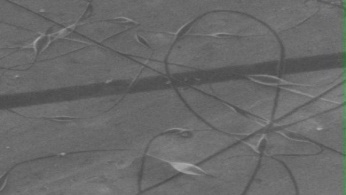

Morphology analysis was adapted from Aytac et al. (2019) [38]. The SEM analysis was conducted to detect electrospun nanofibers' fibre shape and diameter. The electrospun nanofibres from 18 runs were investigated individually by SEM (FEI, quanta 450, Czech). Images revealed the morphology of resultant nanofibers and measured their diameters in nanometres. The average number of records was calculated using a standard deviation estimation. The setting of the SEM machine was conducted on voltage 25.00 kv, magnification 23624 and width (8.3-9.3 mm).

Results of the SEM analysis are listed in table 2, with a wide range of fibre diameters starting from 87.2 nm (run 13) to 2500 nm (run 18). Run 18 did not produce true nanofibers due to the deficient concentration of PVA. The statistical analysis revealed that the effect of each polymer (factor) on the diameter size of the electrospun nanofiber was vast. Therefore, there is a correlation between factors A, B and C and fibre diameter as expressed in equation 5.

Fig. 3: Nanofibres SEM images with nanofiber diameter frequencies. The PVA, PEO and HPMC were symbolised as V, E and P. Data are given in mean±SD, n=3

The morphology of nanofibers would be affected by device parameters such as flow rate, voltage and distance from the collector. Also, nanofibres' properties could be changed due to temperature and humidity. The bead formation appears with a low concentration of PVA (run 2) or a high concentration of PEO and HPMC (runs 6 and 11), as shown in fig. 3. Therefore, increasing PVA concentration leads to beads' disappearance and smooth fibres' formation. Nageeb El-Helaly (2021) and Silva J. A. et al. (2021) reported similar results [47, 48]. Kalluriet al.(2021)[49] studied the relationship between the fibre diameter, bead diameter and flow rate. Thus, they concluded that better fibre uniformity and bead formation were needed at a high flow rate. These results appear clearly in run two and run six and agree with Silva et al.(2021) results [50], who reported that only the concentration of PVA (≥ 15%) could produce uniform nanofibers when using the lower molecular weight of PVA (67,000). Fibre diameter of 15% PVA and more appeared to be in the range 87.11 to 252.5 nm with uniform fibres and disappearance of beads except in run 6, where the beads appear due to increasing the concentration of HPMC as highlighted by Gripet al. (2018) [46].